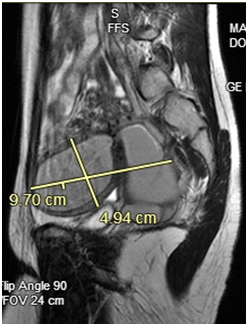

Figure 2 Patient 1: Pelvic MRI: A normal-appearing uterine horn is seen in the left pelvis measuring 4.2 x 1.7 x 2.1 cm. A 9.7 x 4.9 x 4.7 cm lobular tubular thick wall cystic structure in the right pelvis is seen. Signal intensity suggests hemorrhagic contents. This lesion is contiguous with a similar but smaller dilated tubular structure extending to the right aspect of the posterior vagina. Findings are suspicious for uterine didelphys with hematometra of the right-sided uterine horn and cervix.

In all three cases pelvic ultrasound was initial imaging tool. The ultrasound in case 1 (Figure 1) and subsequent MRI (Figure 2) shows a lobular tubular thick wall cystic structure in the right pelvis suggesting hemorrhagic contents extending into the right aspect of the posterior vagina and didelphys uterus. MRI of the abdomen depicts renal agenesis, demonstrating abnormal kidney development confirming HWW. As per the classification presented by Zhu and imaging, the patient has a class 1.2 OHVIRA.2 The ultrasounds in cases 2 and 3 (Figures 6 & 9 respectively) both demonstrate didelphys uterus with two cervices. The additional MRI in case 2, revealed two separate cervices and two uteri one with a retained IUD. MDA can be associated with a vaginal septum, more commonly vertical (Case 2 & Figure 5) but cases of a horizontal septum have also been reported (Case 1 & Figure 8).14